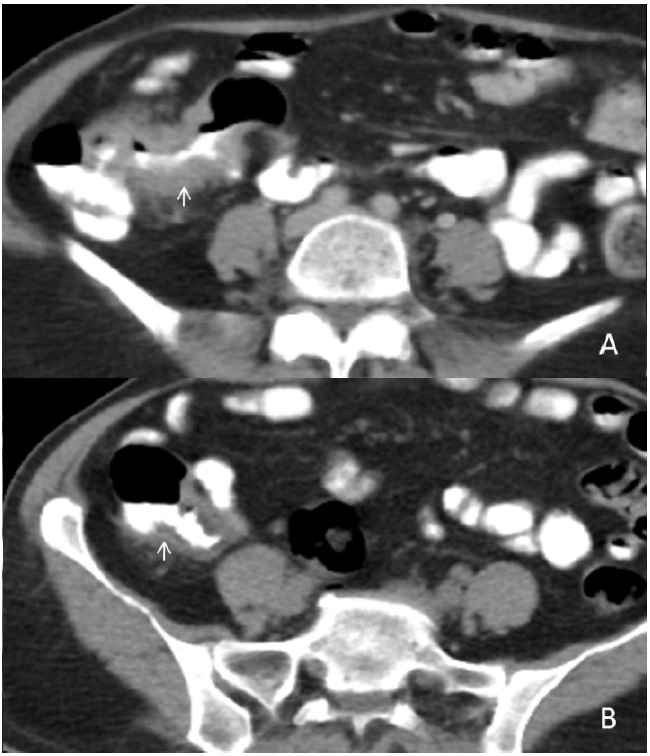

Tubercular lymphadenitis

Lymphadenopathy is the commonest finding associated with abdominal tuberculosis. A wide range of patterns can be seen, including an increase in the number of lymph nodes to large nodal masses. The commonly involved lymph nodes groups are omental, mesenteric, celiac, portahepatis and peripancreatic. The conglomerated pattern of lymph nodes is commonly seen in abdominal tuberculosis. In contrast, CT features of involved lymph nodes may vary from peripherally enhancing lymph nodes with low-density centres (signifies caseous necrosis) to homogeneous/heterogeneous enhancement. Lymph nodes calcification is also seen in chronic tubercular infection (Figure 1A,1B). The necrotic lymph nodes are not pathognomic for tuberculosis as they can also be seen in metastasis, lymphoma or Whipple’s disease [4].

Figure 1: (A) A 30 years old male patient came with a complaint of vague pain abdomen, low-grade fever and a history of significant weight loss in the recent past. On physical examination, there was diffuse pain in the abdomen without any organomegaly. Postcontrast computed tomography image from a venous phase in the axial plane illustrates multiple, conglomerated, peripherally enhancing para-aortic (white arrow) & mesenteric (black arrow) lymph nodes with central necrosis. (B) In another 60 years old male patient with similar complaints, a post-contrast computed tomography image from a venous phase in the axial plane shows heterogeneously enhancing, enlarged, and conglomerated lymph node masses with internal low attenuating areas and punctate calcification (thick white arrow) in the left para-aortic region. Both these patients were diagnosed with TB on CT guided lymph node FNAC and anti-tubercular therapy was started. Patients are now symptomatically better and kept on follow up.